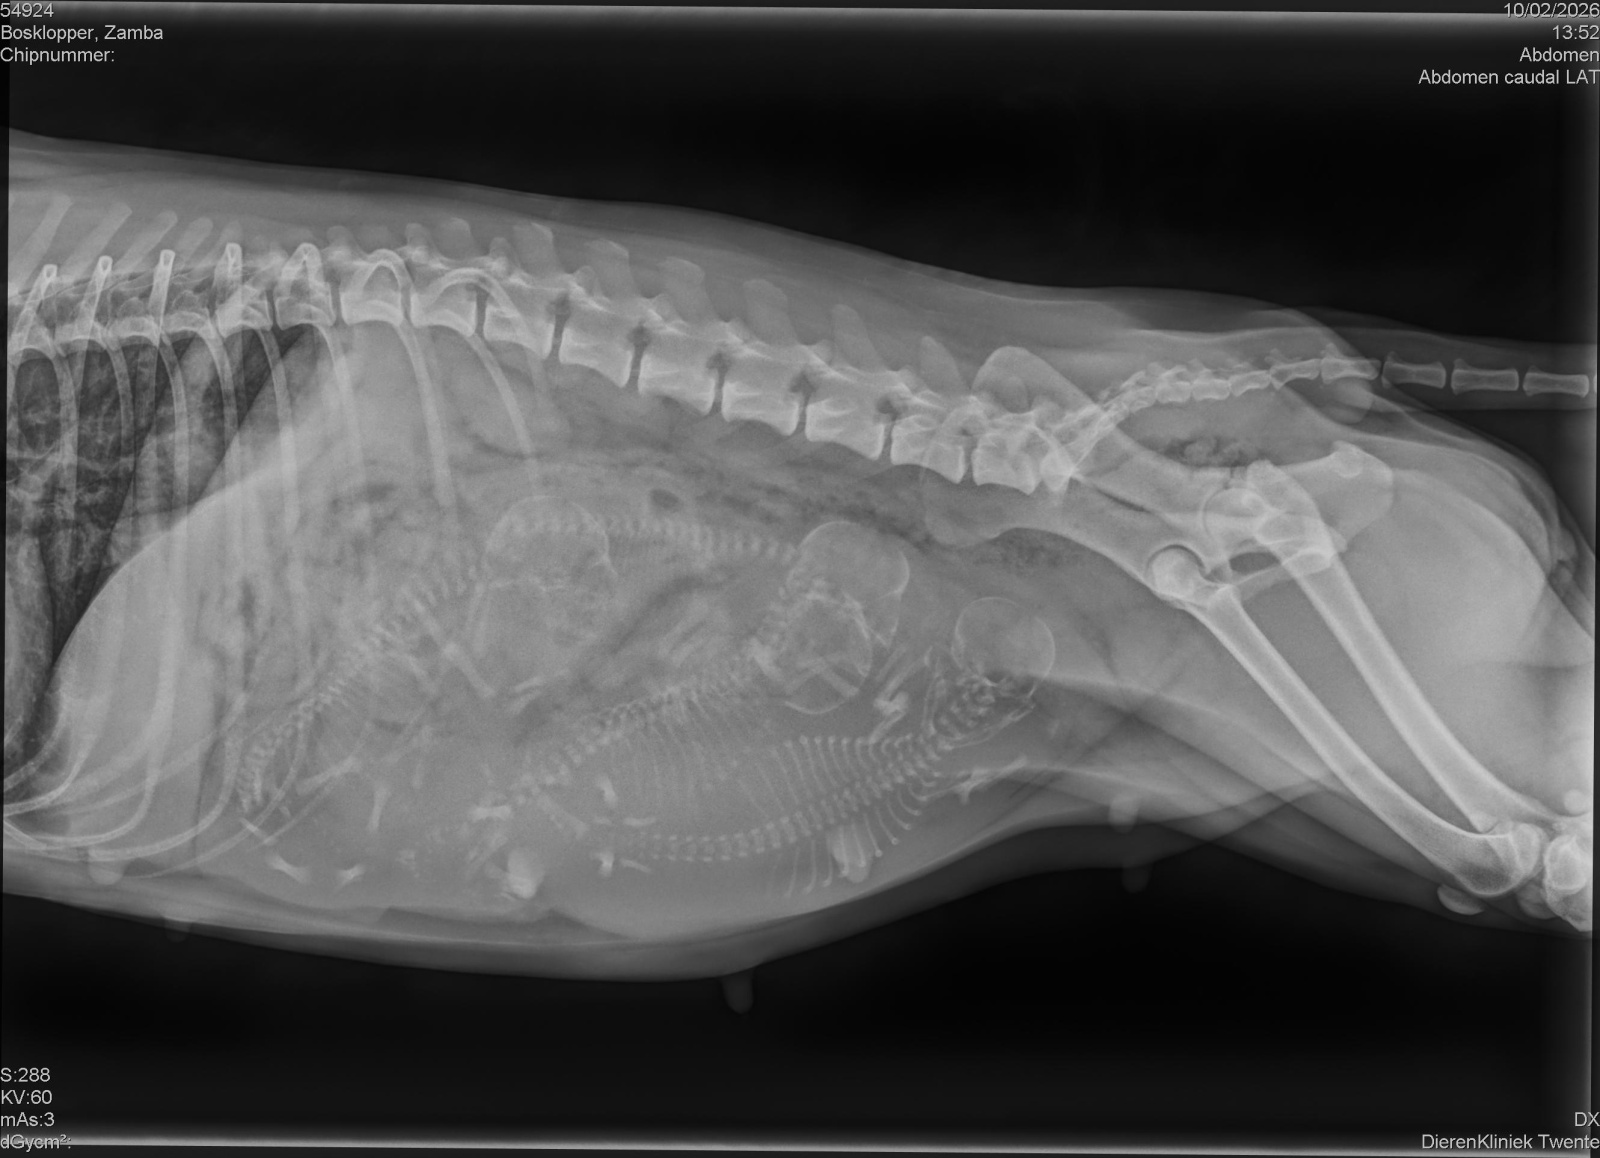

Op 14 januari 2026 is bij Dierenkliniek Twente in Enschede een echo gemaakt van Dazzling Flash Zamba. Tijdens dit onderzoek werd bevestigd dat zij dragend is. Alles ziet er op dit moment goed en gezond uit.

Op basis van de echo is de verwachting dat er waarschijnlijk vier pups onderweg zijn. Een echo blijft altijd een momentopname, maar de bevindingen geven een positief en geruststellend beeld van het verloop van de dracht tot nu toe.

Echo van de dracht bij Dazzling Flash Zamba, januari 2026Echo van de dracht bij Dazzling Flash Zamba, januari 2026